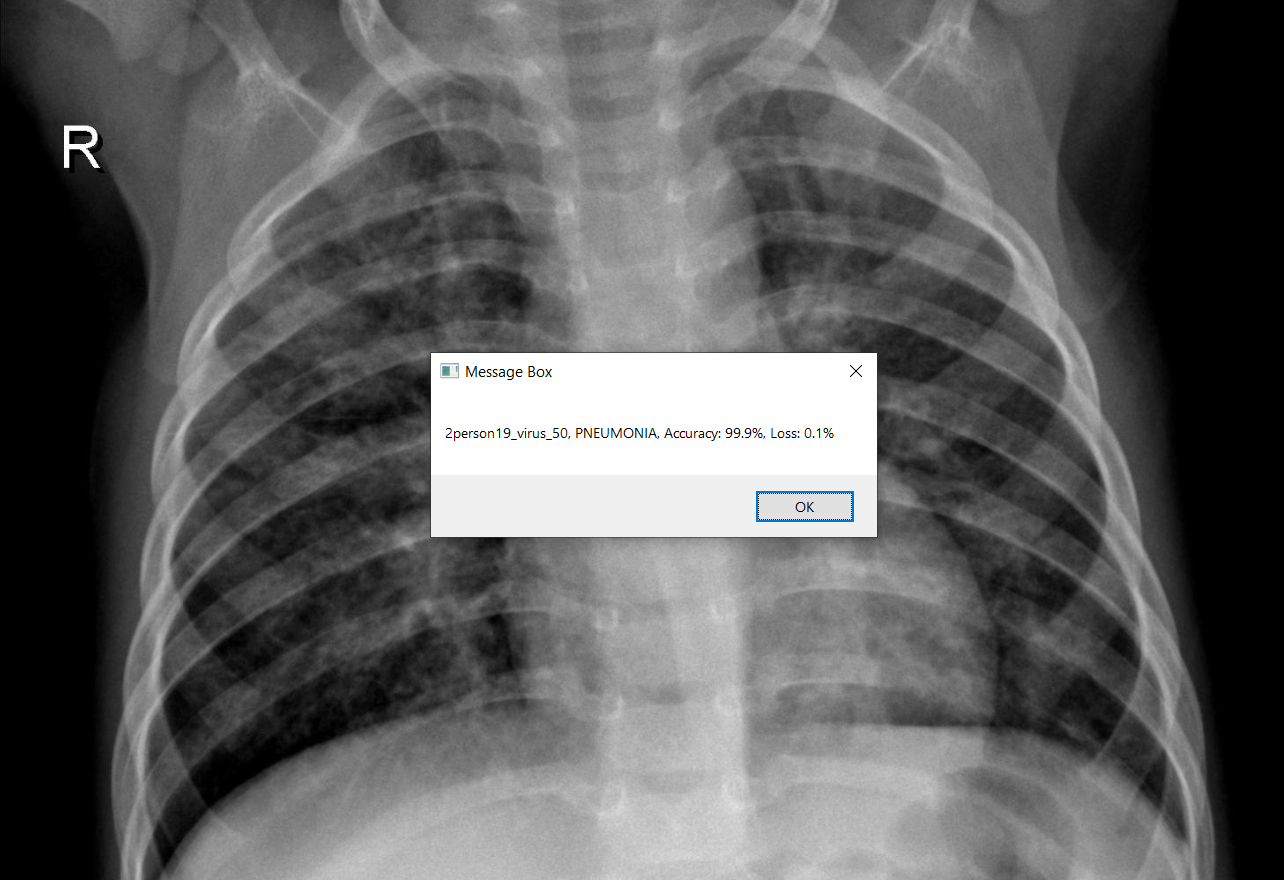

UIPath: After saving the best deep learning model, I built a workflow in UIPath to automate my testing process. The workflow will load the deep learning model, ask the users to select their chest Xray image and use the pre-trained model to test on the selected image. The diagnosis results will be displayed in a message box along with the selected image. All results will be saved into a log so that users can keep track of their testing process.